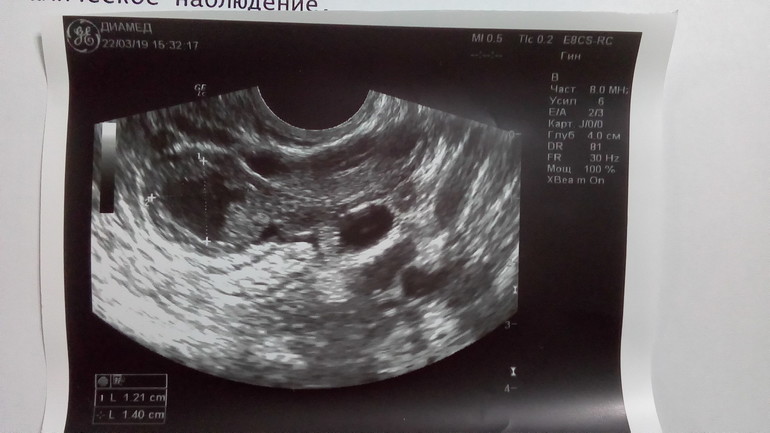

узи

8 день задержки узи 118 фотографий